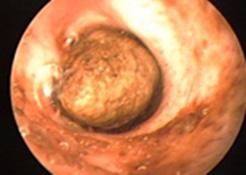

Al examen otoscopio se puede visualizar. Su textura puede ser líquida hasta duro como una roca. El color varía de un rojo oscuro profundo a negro a blanquecino. Un individuo determinado puede tener cerumen de diferente color en cada oído. El color del cerumen refleja su composición, pero no necesariamente representa la normalidad o la salud del canal externo.

Figura 8. Otoscopía de un CAE con cerumen impactado